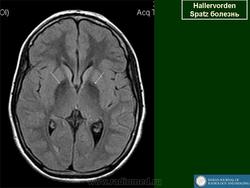

Галлервордена - Шпатца болезнь (J. Hallervorden, 1882-1965, нем. невропатолог; H. Spatz, совр. нем. невропатолог; син. ригидность прогрессирующая) - наследственная болезнь, связанная с нарушением обмена железа и липидов, проявляющаяся в возрасте 7-9 лет повышением мышечного тонуса, гиперкинезами, прогрессирующей деменцией, снижением зрения и пигментным ретинитом; наследуется по аутосомно-рецессивному типу.

Болезнь Галлервордена - Шпатца - наследственное заболевание экстрапирамидной системы, связанная с нарушением обмена железа и липидов и повреждением бледного шара и черной субстанции. Тип наследования аутосомно-рецессивный. При патоморфологическом исследовании характерным признаком является гиперпигментация бледного шара и черной субстанции. Обнаруживается пигментация коры полушарий большого мозга и таламуса. Пигмент находится внутри невронов и глиальных клеток, расположенных около сосудов; содержит железо (вместе с тем каких-либо нарушений обмена железа в организме не обнаружено). Наблюдаются утолщение и фрагментация аксонцилиндров в пораженных областях. Постепенно наступает дегенерация невронов коры полушарий большого мозга и мозжечка. Характеризуются нарастающей экстрапирамидной ригидностью, гиперкинезами (атетоз, торсионная дистония), затем развивается акинетико-ригидный синдром, пирамидная микросимптоматика, снижение интеллекта. Течение медленно прогрессирующее на протяжении 10 - 20 лет.

Клиническая картина. Заболевание начинается с прогрессирующего нарушения походки и ригидности в ногах, замедления и уменьшения объема произвольных движений, дизартрии и задержки умственного развития. У 50 % больных появляются хореиформные и атетоидные движения. Постепенно развиваются спастичность и атрофия дистальных отделов конечностей, признаки деменции. У больных нередко обнаруживают пигментный ретинит или атрофию зрительных нервов. Прогноз неблагоприятный.

"Глаз тигра"-наглядно и красиво.